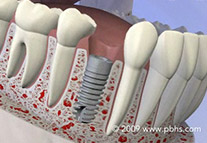

• Dental Implants

Dental Implants